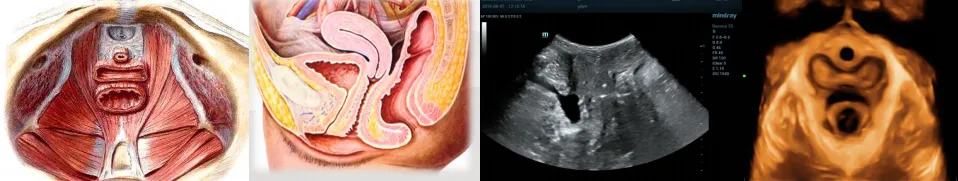

它是指由于盆底肌肉、韧带、筋膜等支持结构变得薄弱、损伤或功能不协调,导致其承托的盆腔器官(膀胱、子宫、直肠等)无法维持在正常位置,进而引发一系列症状的综合征。简单来说,可以做一个比喻:您体内的盆底肌就像一张富有弹性的“吊床”,稳稳地托着膀胱、子宫和直肠。当这张“吊床”因为各种原因变得松弛、撕裂或失去弹性后,它托着的东西就会下沉(脱垂),或者原本由它控制的“开关”会失灵(引起漏尿、排便困难等)。

盆底超声是一种无创、无辐射、高分辨率的影像技术。通过会阴部超声探头,可以动态观察:盆底肌群是否松弛或损伤;子宫、膀胱、直肠是否脱垂;排尿/排便功能是否异常;术前评估及术后康复效果。

蚌埠市第四人民医院高新院区功能科自2024年开展盆底超声检查以来,已为300余名患者进行盆底四维超声检查,检出压力性尿失禁、盆腔各种不同程度的脱垂及盆腔脏器的一些疾病,能早期发现、早期诊断盆底功能障碍性疾病,准确地评估妊娠和分娩后盆底支持结构的改变,如盆腔器官有无脱垂、肛提肌有无损伤或撕裂等。我院康美中心已形成完善的盆底检查、手术治疗、康复一体化诊疗体系,为广大女性筛查盆底功能障碍性疾病。